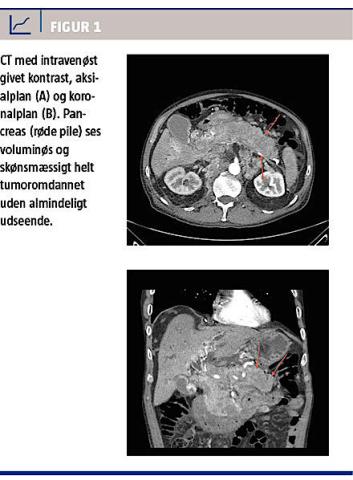

Niveauerne af basisk fosfatase og bilirubin var let forhøjede. Amylase- og glukoseniveauerne var normale. Ved UL-skanning påviste man en tumoromdannet pancreas (Figur 1). CT af thorax og abdomen

viste metastasering til binyrer, nyrer, pancreas og lymfeknuder ingvinalt og retroperitonealt samt i venstre aksil og mesenteriet. Palliativt blev der foretaget endoskopisk retrograd kolangiopankreatografi med indsættelse af endostent, ascitesdrænage og diuretisk behandling af bilateral pleuraeffusion. Biopsi fra tumormassen i pancreas viste et lavt differentieret adenokarcinom udgående fra prostata. Farvning med